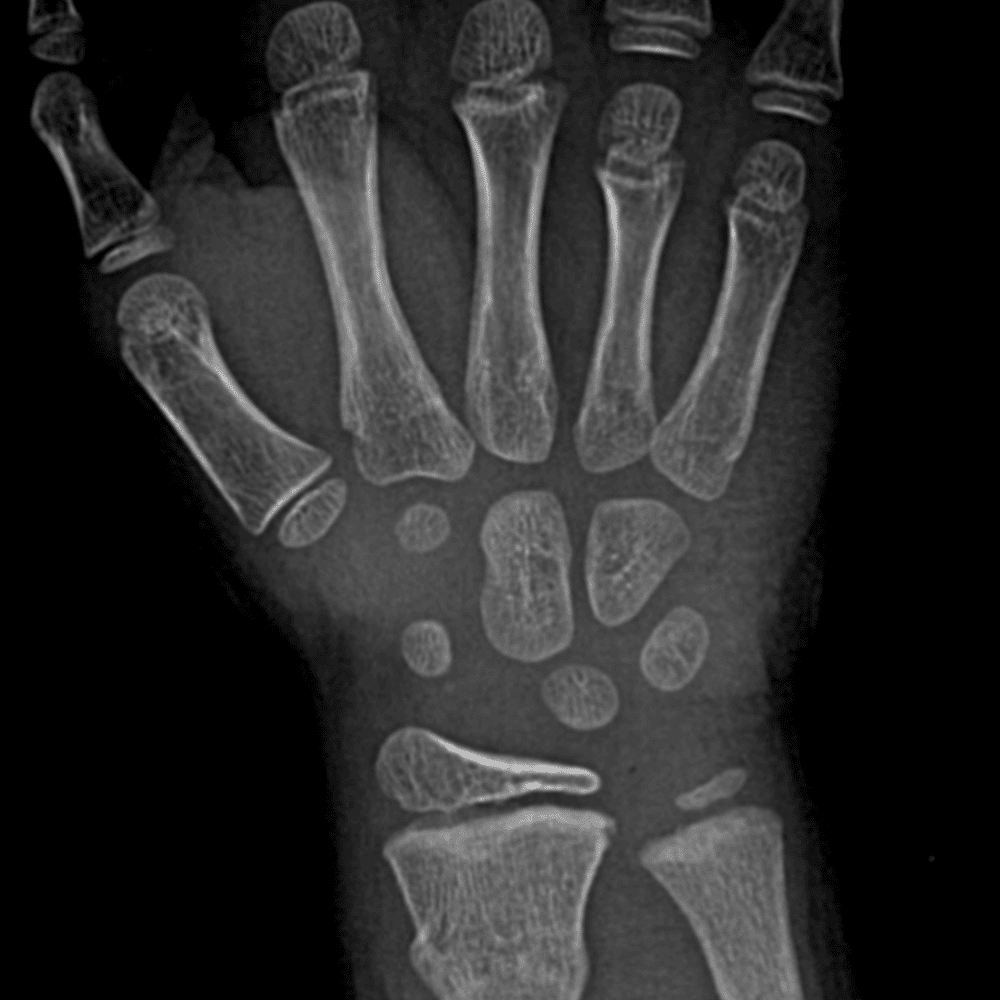

Simulates call by including subtle or difficult cases and some normals.

30 cases